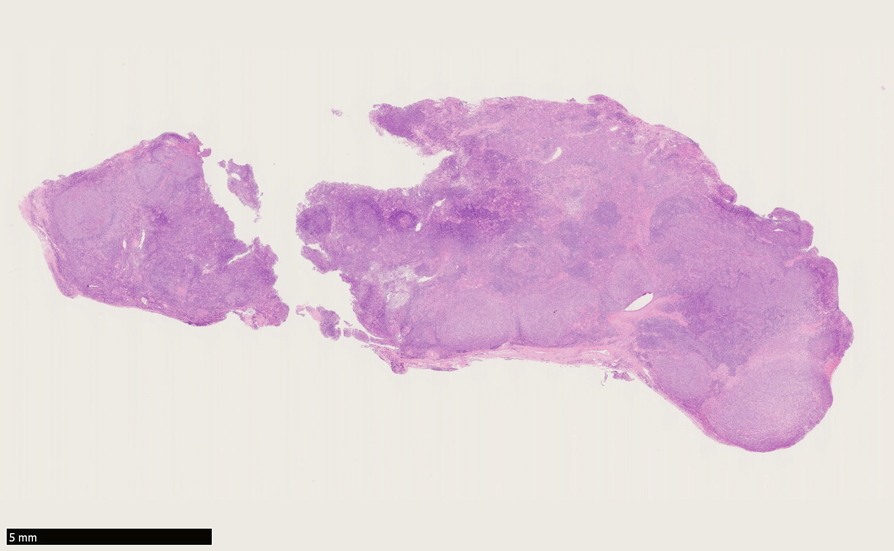

左甲状腺腫瘤部分切除生検

Urk-thyroid-loupe01.jpg

生検組織loupe像:濾胞構造が明瞭な腫瘤病変.

検鏡後病理診断: thyroid MALT lymphoma with follicular colonization

症例02: 濾胞性増殖の顕著な甲状腺リンパ腫の1例 76歳女性 甲状腺, 磐田市立総合病院 病理診断科 副院長 谷岡 書彦